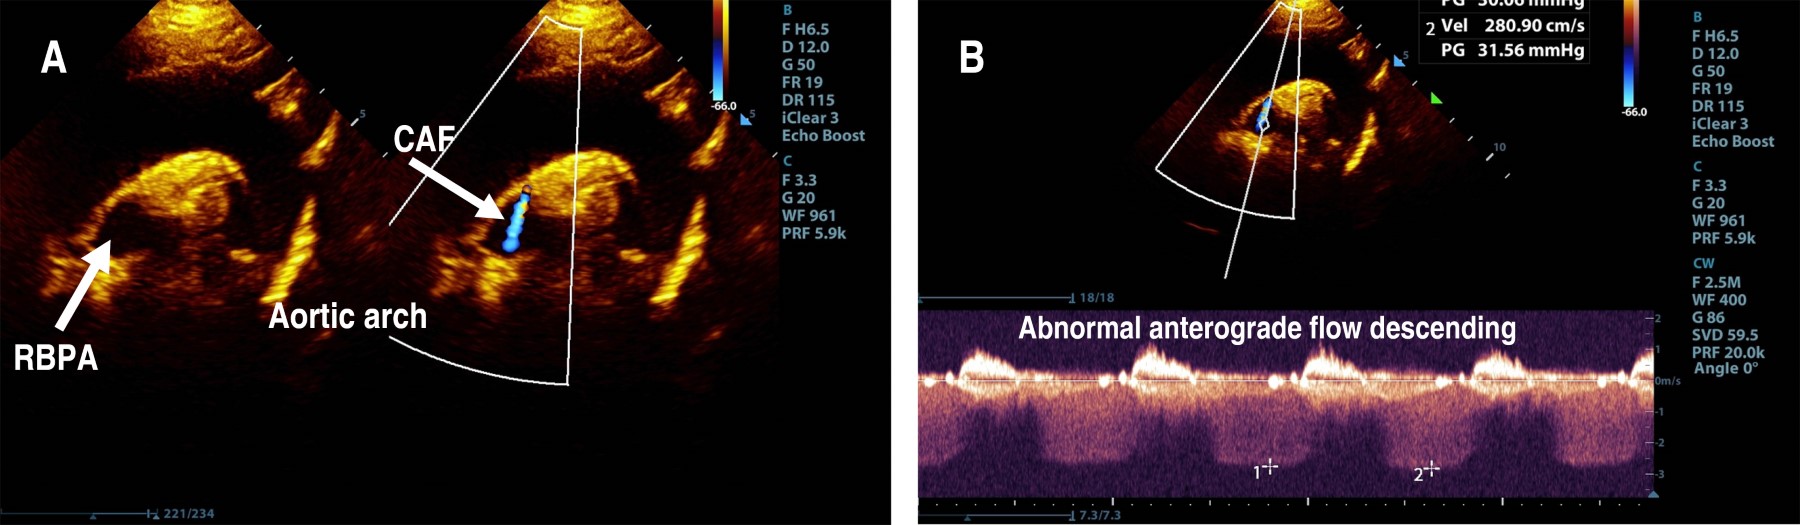

The parasternal short-axis view of the aortic root showed the right coronary artery (RCA) and left coronary artery (LCA) in their appropriate anatomical positions, with the proximal segment of the RCA exhibiting a Z score of 0.2 (Figure 1). However, the suprasternal longitudinal view identified an abnormal vascular structure with anterograde flow descending into the right branch of the pulmonary artery (RBPA) (Figure 2). The suprasternal short-axis view illustrated an anastomosis at the proximal segment of the RBPA, characterized by continuous, pulsatile flow, a maximum recorded velocity of 2.8 m/s, and a maximum gradient of 31 mmHg (Figure 3).